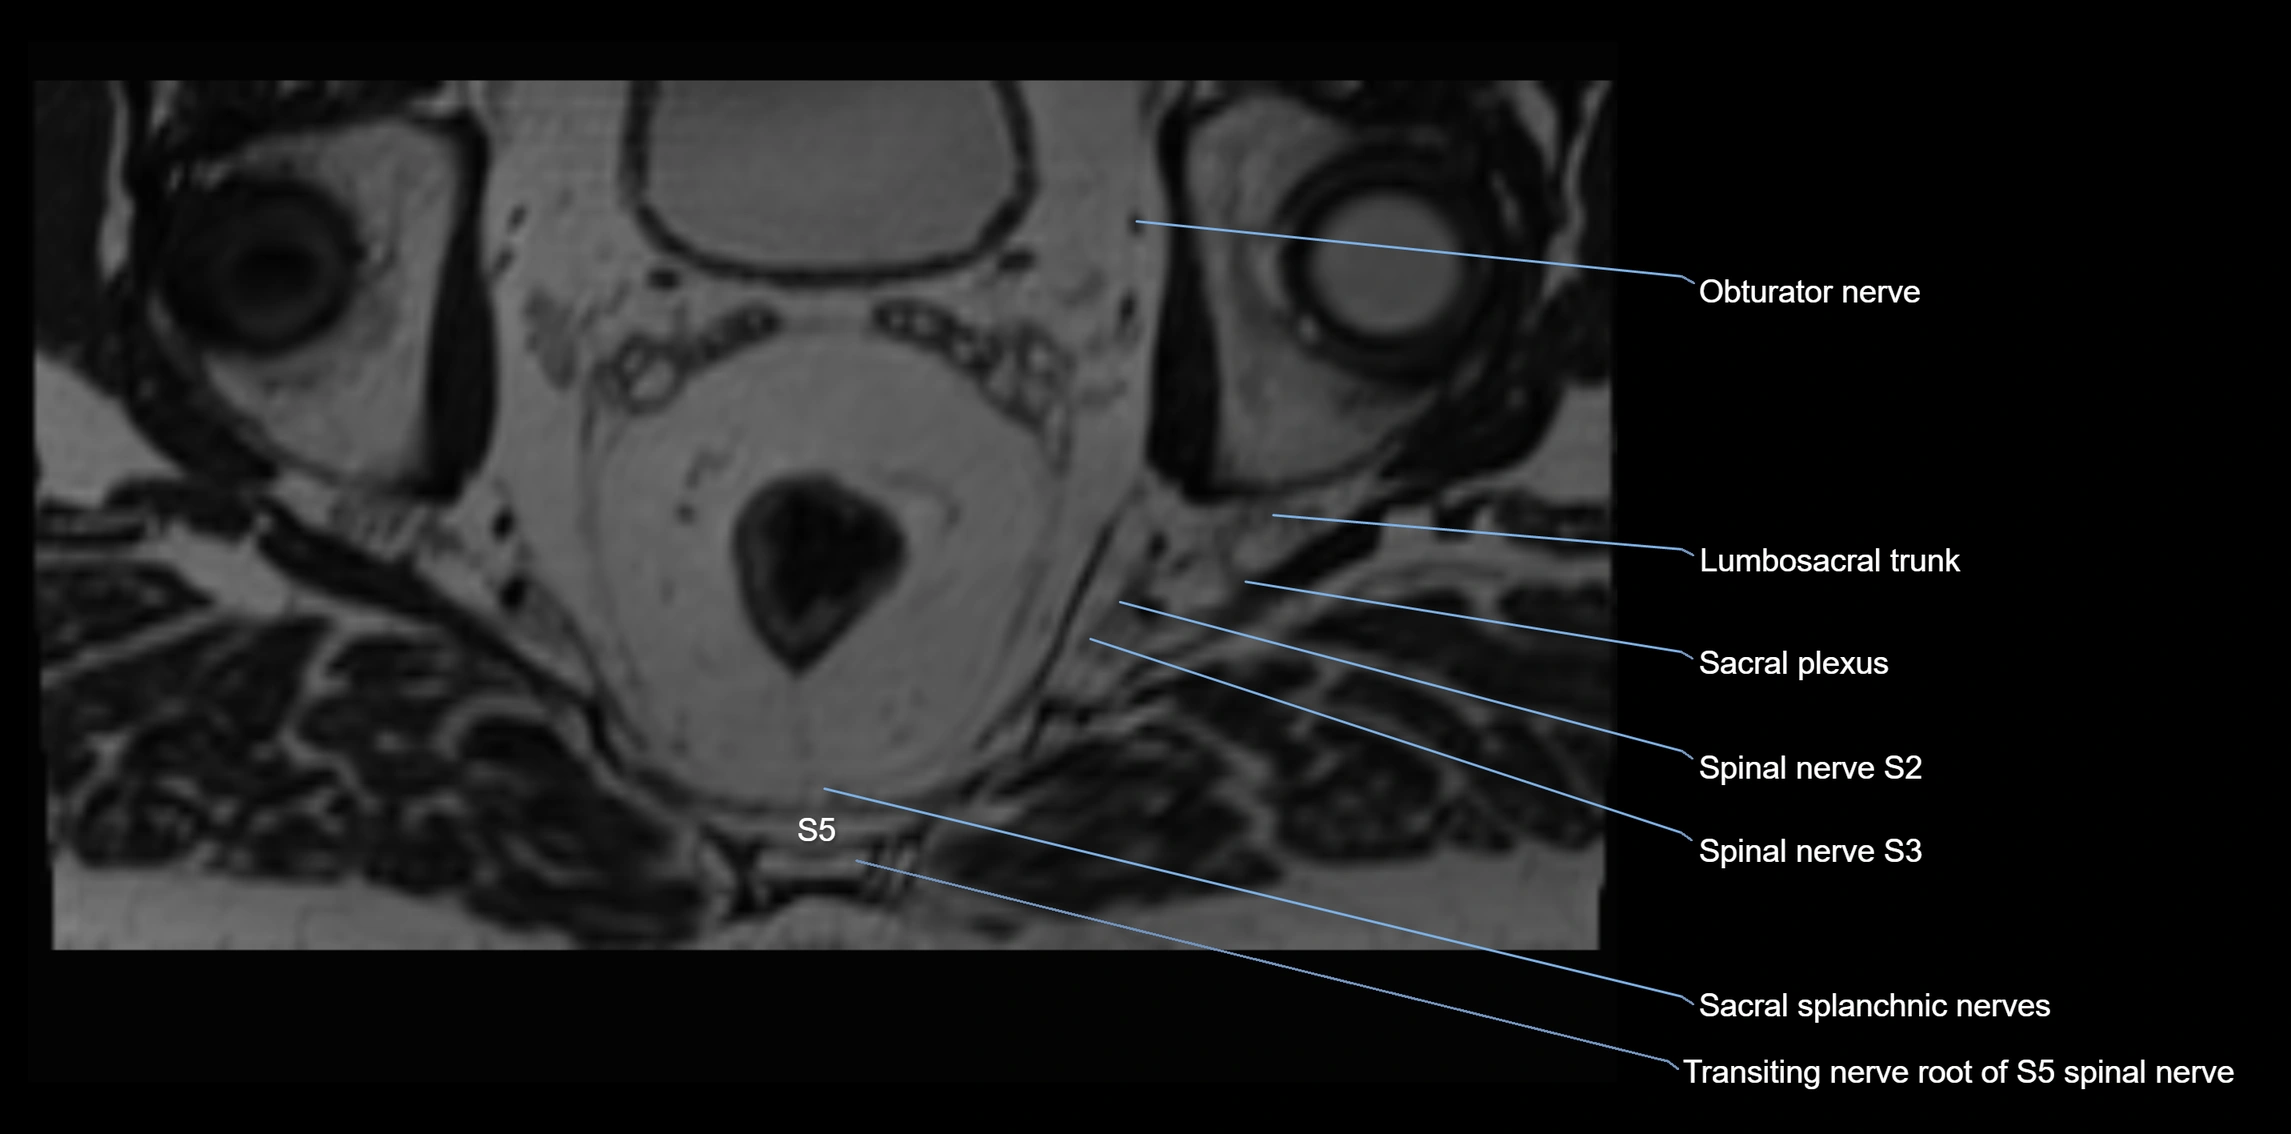

MRI Appearance

T1-weighted images:

• Nerve appears as a very thin low-to-intermediate signal intensity structure

• Surrounded by bright fat, aiding visualization

T2-weighted images:

• Nerve shows intermediate to mildly hyperintense signal compared to muscle

• Pathological involvement appears brighter

STIR (Short Tau Inversion Recovery):

• Normal nerve appears dark

• Inflamed or entrapped nerve appears bright hyperintense

T1 Fat-Sat Post-Contrast:

• Normal nerve enhances minimally

• Pathologic nerve (neuritis, entrapment, tumor infiltration) shows focal or diffuse enhancement

3D T2 SPACE / CISS:

• Nerve appears intermediate to mildly hyperintense compared to muscle

• Surrounded by bright fat or CSF, improving visualization

• Best sequence for mapping small pelvic nerves such as the anococcygeal